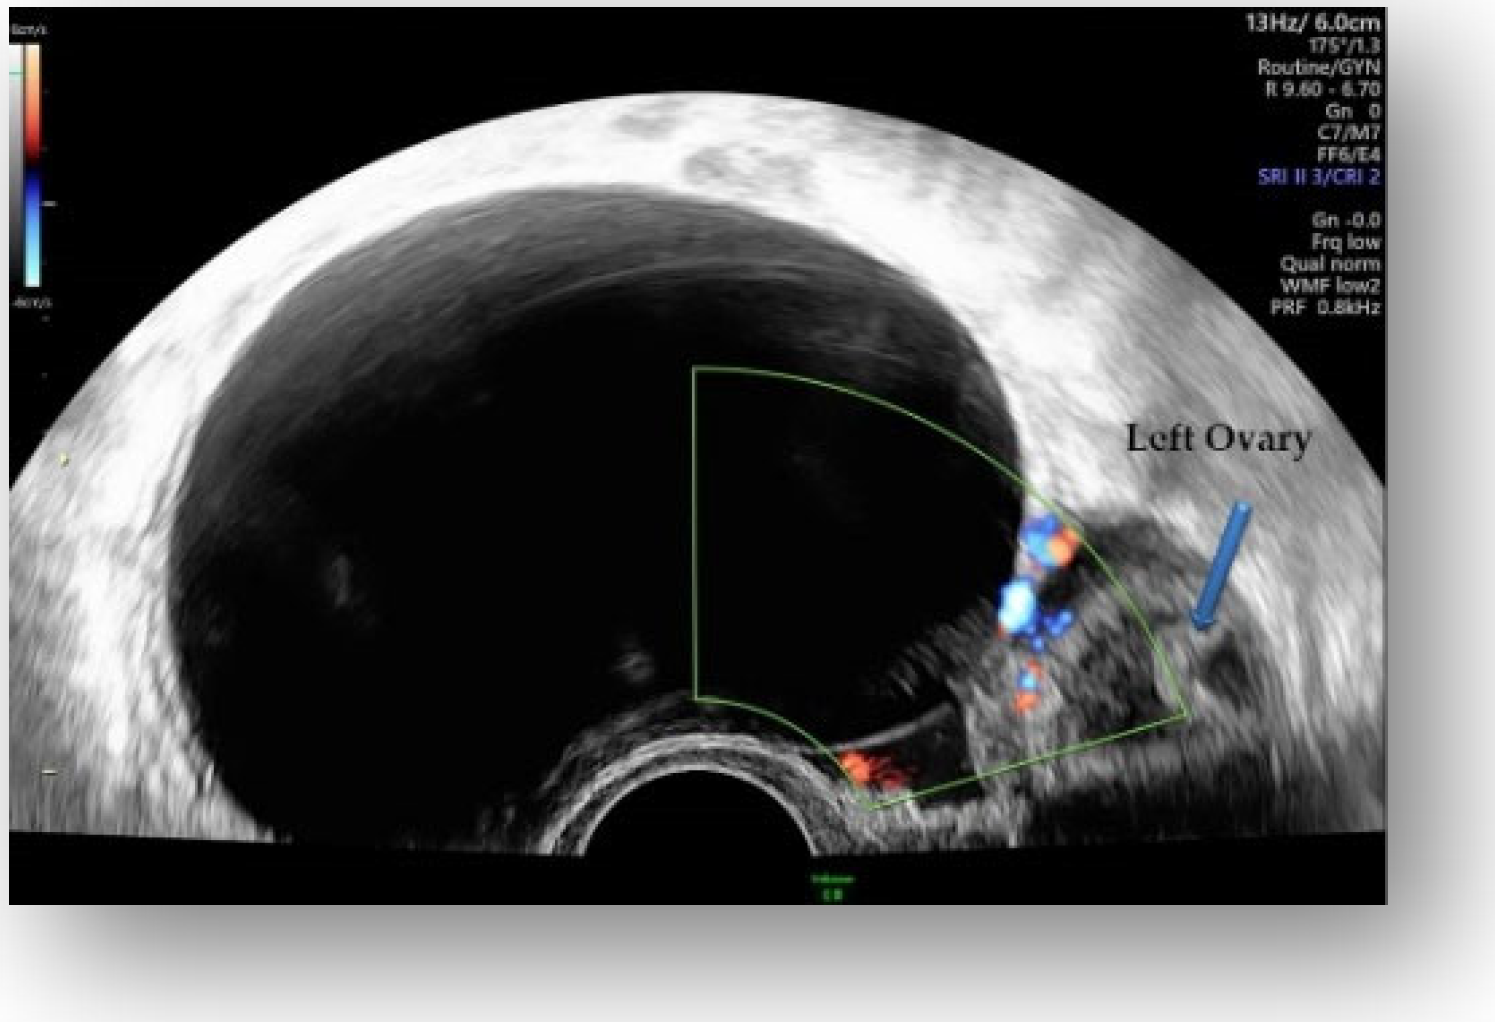

2.4. Diagnostic Assessment and Investigations